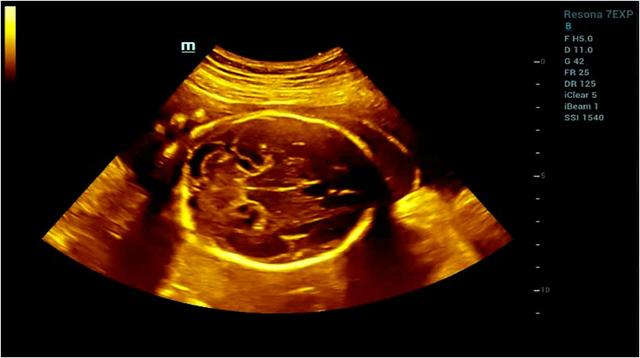

如何解决医生人手不足与孕产妇排长队的冲突?毋庸置疑,简单实用的智能超声系统就格外重要。在超声检查中,比如二维超声、多普勒超声、介入超声、三维超声,这些传统超声成像方法是通过“线扫描”技术成像,这意味着超声图像分辨率取决于发射频率。然而,随着发射频率增加到一定水平,分辨率很难再有显著提升。传统超声受空间分辨率、时间分辨力和组织均匀性三个参数的互相限制,若单提高一个则会牺牲其他及最终图像质量。所以传统超声形成的图像,朦胧,似真非真,依赖医生诊断经验,需要我们较长时间才能辩认,对诊断治疗出具检查结果带来较大难度。

而智能超声系统,就突破了传统超声波束合成在成像空间分辨力和时间分辨力的技术限制,扫描成像速度更快,提升了图像的时间帧频,减少了图像的运动伪像;提升了图像整体的均匀一致性,使我们不再需要为了图像的均匀性而频繁的调节焦点。而且通过图像智能算法判决,实现对于不同声速组织图像的最佳呈现,大大提高了图像呈现的速度和清晰度。

目前应用在临床领域的智能化超声,以国内的迈瑞智能化超声系统为代表,其图像清晰可见、一目了然,快速诊断,为医生和患者节省了时间,提升了诊治的效率,最大化提升了医生与医院的就诊效率。

自动切面识别——产科自动容积导航